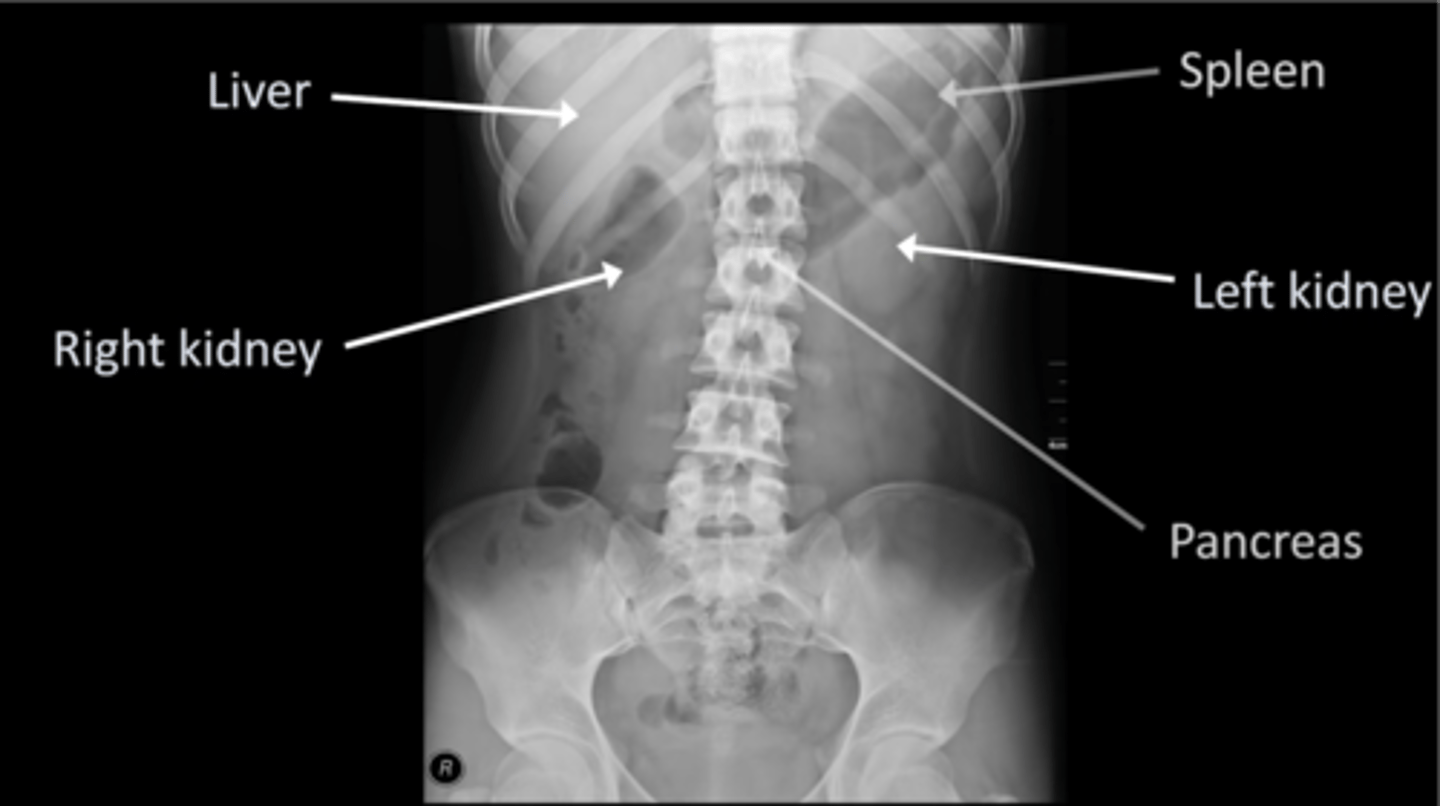

Normal AXR (and normal organs)

Normal AXR (and normal structures)